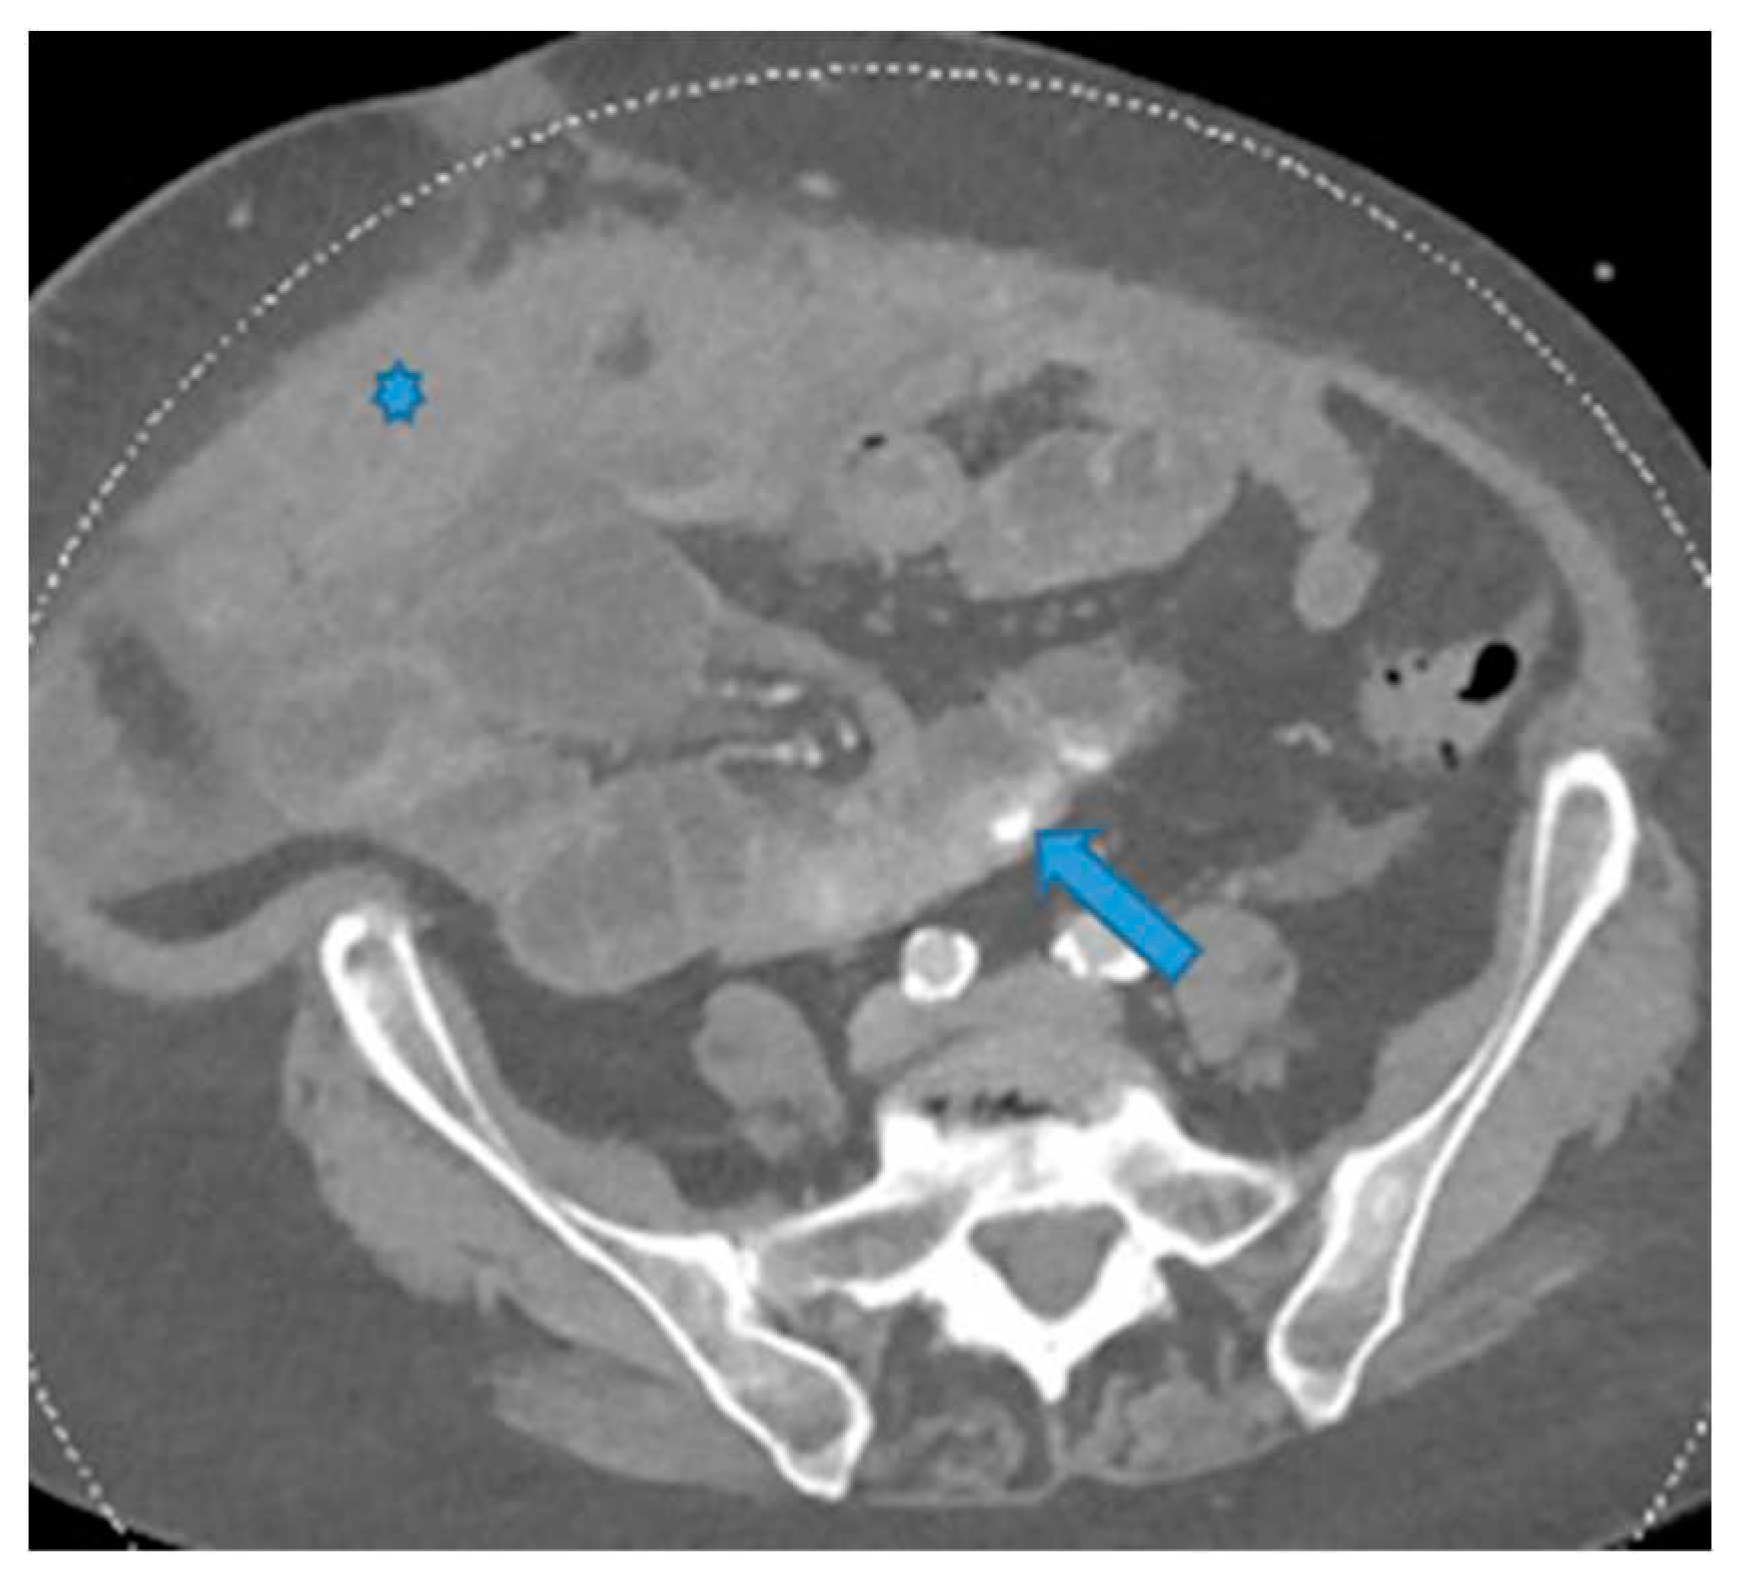

Figure 23.

Axial CE-CT. PC from ovarian carcinoma: mesenteric seeding. Mesenteric involvement may happen as a combination of deposits involving both the mesentery and the bowel serosa, as in this case. Observe the clustered SB loops appearance. The calcified content of some of the deposits enhances their presence (arrow). Omental deposits (*).